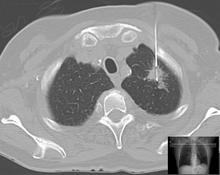

Lung biopsy in a case of suspected lung cancer under control of computed tomography.

When cancer is suspected, a variety of biopsy techniques can be applied. An excisional biopsy is an attempt to remove an entire lesion. When the specimen is evaluated, in addition to diagnosis, the amount of uninvolved tissue around the lesion, the surgical margin of the specimen is examined to see if the disease has spread beyond the area biopsied. "Clear margins" or "negative margins" means that no disease was found at the edges of the biopsy specimen. "Positive margins" means that disease was found, and a wider excision may be needed, depending on the diagnosis.[citation needed]